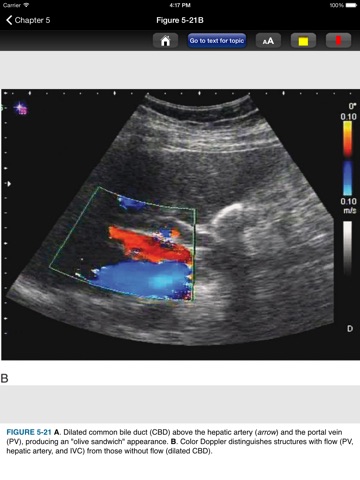

This app provides a quick and handy guide to all the body systems evaluated with ultrasound. This app contains 443 images including photographs showing where to place the ultrasound probe, the actual ultrasound images and explanatory anatomical drawings. This app is derived from the pocket guide to the book Emergency Ultrasound, the most widely used reference and educational tool on the subject. This handy app is a great educational reference for accurately performing and interpreting ultrasound images. The bulleted text details essentials such as clinical considerations, clinical indications, anatomical considerations, tips to improve image acquisition, and technique and normal ultrasound findings. Ultrasound is a rapid noninvasive tool that provides emergency physicians with diagnostic information in real time. Competency in ultrasound can rapidly identify life-threatening conditions and other important clinical diagnoses. Ultrasound is now a requirement in EM residency programs, part of EM physician recertification and why more and more emergency physicians are incorporating its use in their practice. This app is easy to navigate, allowing you to browse the contents or search for topics. The search tool shows you choices of words that appear in the text as you type so it is quick and helps with spelling issues. It also remembers past search terms so you can go back to a topic or image very easily. You can also create notes and bookmarks separately for chapters, images, and tables to enhance your learning. You can also change the text size for easier reading. Check out www.usatinemedia.com to learn more and watch a video demo of this app narrated by Dr. Richard P. Usatine. This interactive app is based on the full content of Pocket Atlas of Emergency Ultrasound by McGraw-Hill. Editors and authors: Robert F. Reardon, MD; Ultrasound Director, Department of Emergency Medicine, Hennepin County Medical Center; Associate Professor, University of Minnesota; Minneapolis, Minnesota James R. Mateer, MD, RDMS O. John Ma, MD Disclaimer: This app is intended for the education of healthcare professionals and not as a diagnostic and treatment reference for the general population. Disclaimer: This app is intended for educational reference only. If you find yourself in an emergency situation, contact a physician. Developed by Usatine Media, LLC Richard P. Usatine, MD, Co-President, Professor of Family & Community Medicine, Professor of Dermatology and Cutaneous Surgery, University of Texas Health Science Center San Antonio Peter Erickson, Co-President, Lead Software Developer